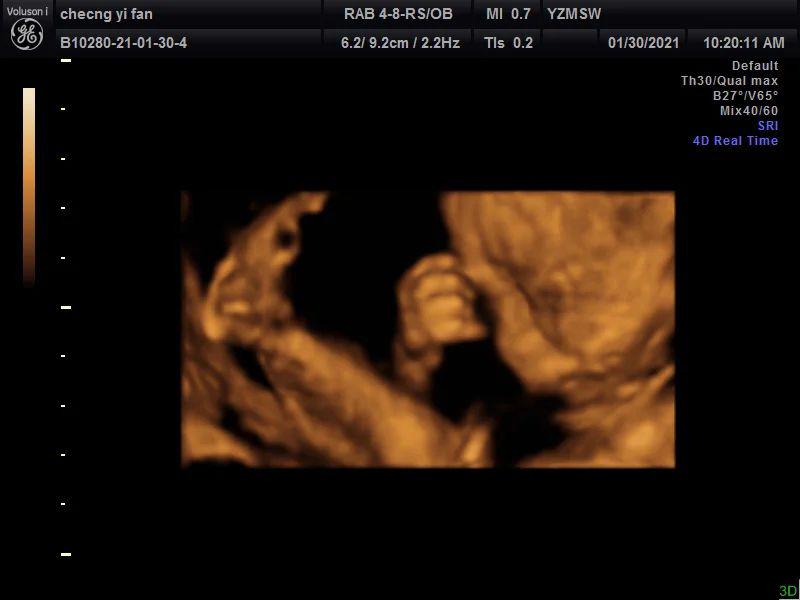

第二天四维是孕23周+4天,约了一个私立医院,主要是可以保存宝宝的照片和视频,于是就去了,这次是早上,宝宝非常配合(图三到图七)!脸和脚,小拳头,都拍的特别清楚,医生说宝宝很好看,尖尖的下巴,鼻梁好好的,眼睛也很大,到最后手放在脸上,还对我比了个✌️嘻嘻嘻,希望四维照片和宝宝出生照像一些~